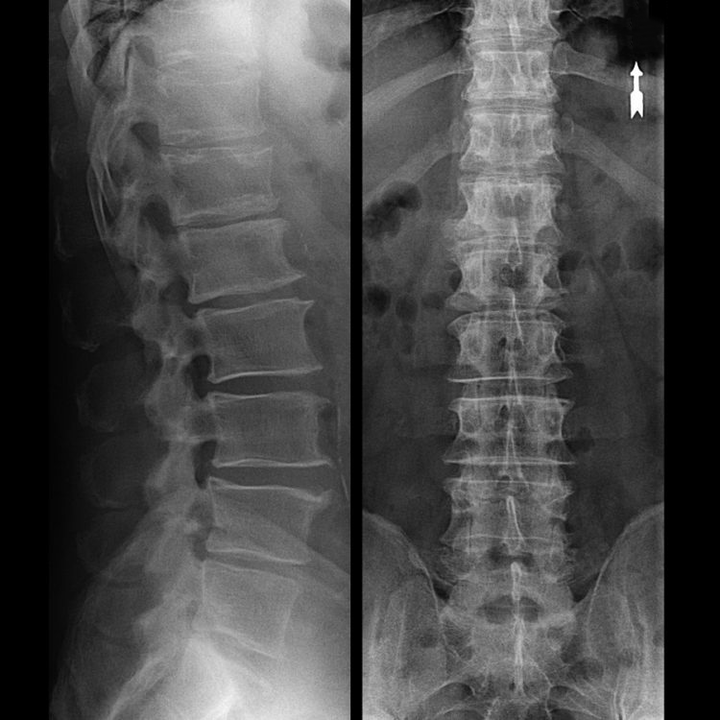

Une « radiographie » de la colonne cervicale, et même avec des tests fonctionnels de flexion et d'extension, ne montre pas de cartilage, car son tissu transmet les rayons X. Malgré cela, sur la base de la localisation des vertèbres, on peut tirer des conclusions générales sur la hauteur des disques intervertébraux, le redressement général de la courbure physiologique du cou - lordose, ainsi que la présence d'excroissances marginales sur les vertèbres avec une irritation prolongée de leurs surfaces par des disques intervertébraux fragiles et déshydratés. Des tests fonctionnels peuvent confirmer le diagnostic d’instabilité du rachis cervical.

Étant donné que les disques eux-mêmes ne peuvent être vus qu'à l'aide de la tomodensitométrie ou de l'IRM, la tomodensitométrie par résonance magnétique et par rayons X est indiquée pour clarifier la structure interne du cartilage et des formations telles que les saillies et les hernies. Ainsi, à l'aide de ces méthodes, un diagnostic est posé avec précision et le résultat de la tomographie est une indication, voire un guide topique, pour le traitement chirurgical d'une hernie dans le service de neurochirurgie.